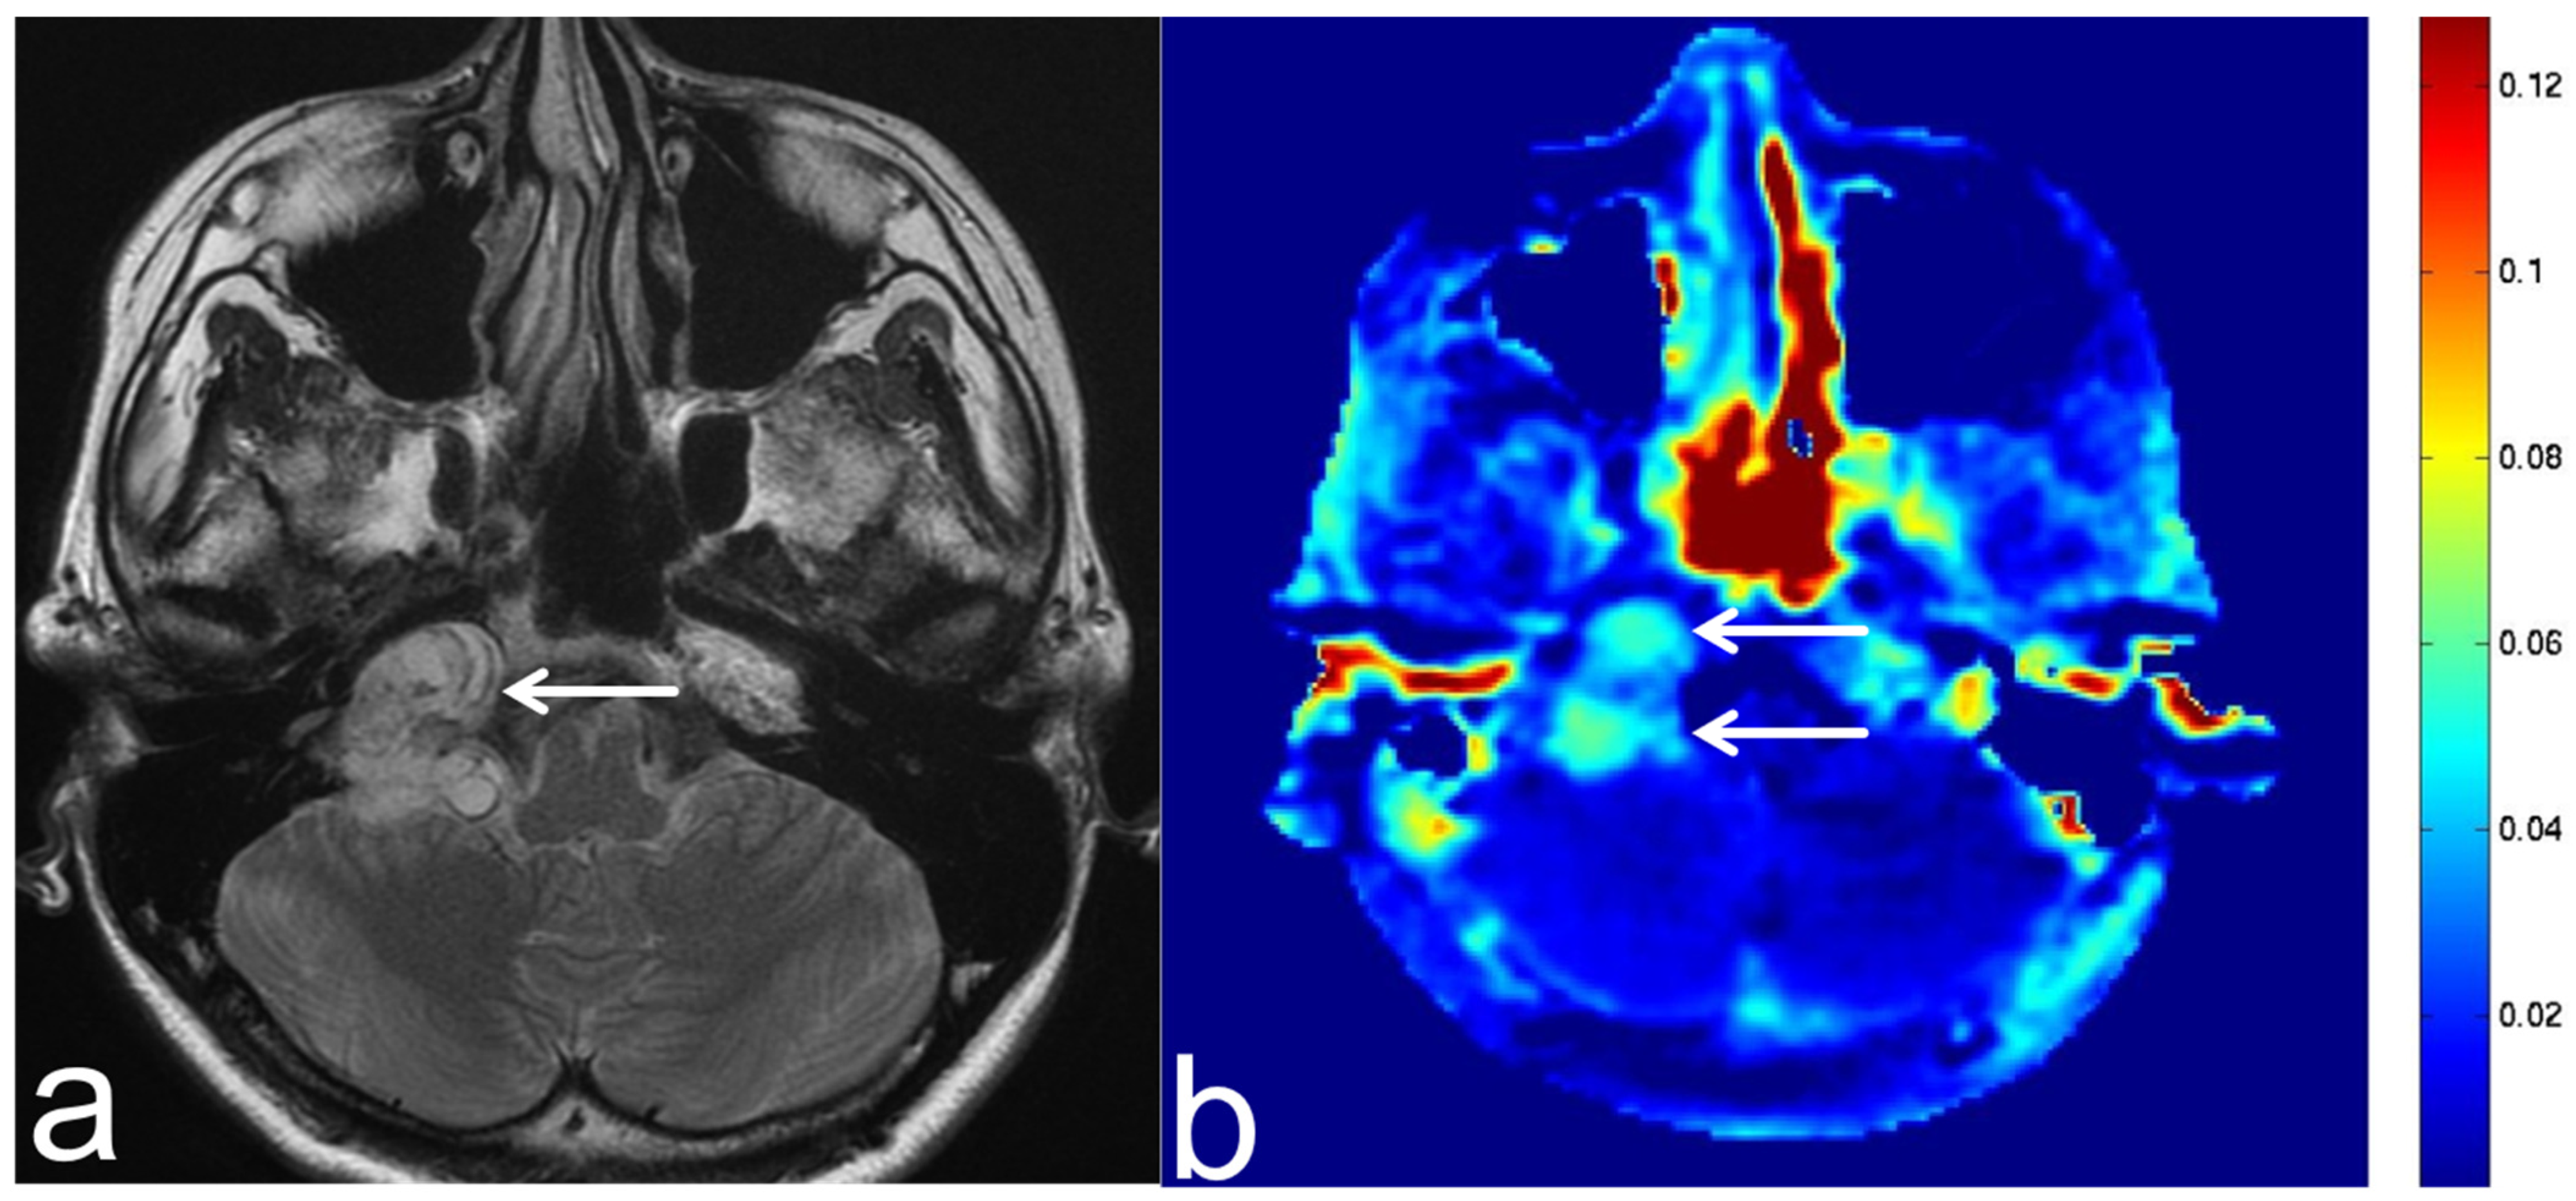

5.3. Glioblastoma

5.5. Brain Metastasis